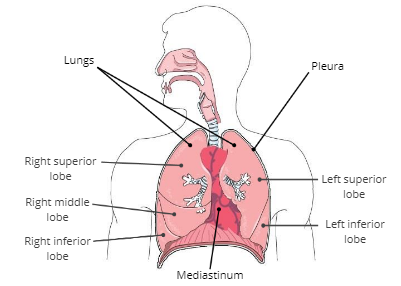

Lungs

soft, spongy organs in the thoracic cavity that are responsible for gas exchange

Mediastinum

a compartment in the center of the thoracic cavity that contains the heart, trachea, and esophagus.

Pleura

a thin, double membrane that surrounds each lung and lines inner surfaces of the thoracic cavity

Pleural fluid

fluid in between the pleura that reduces friction during breathing